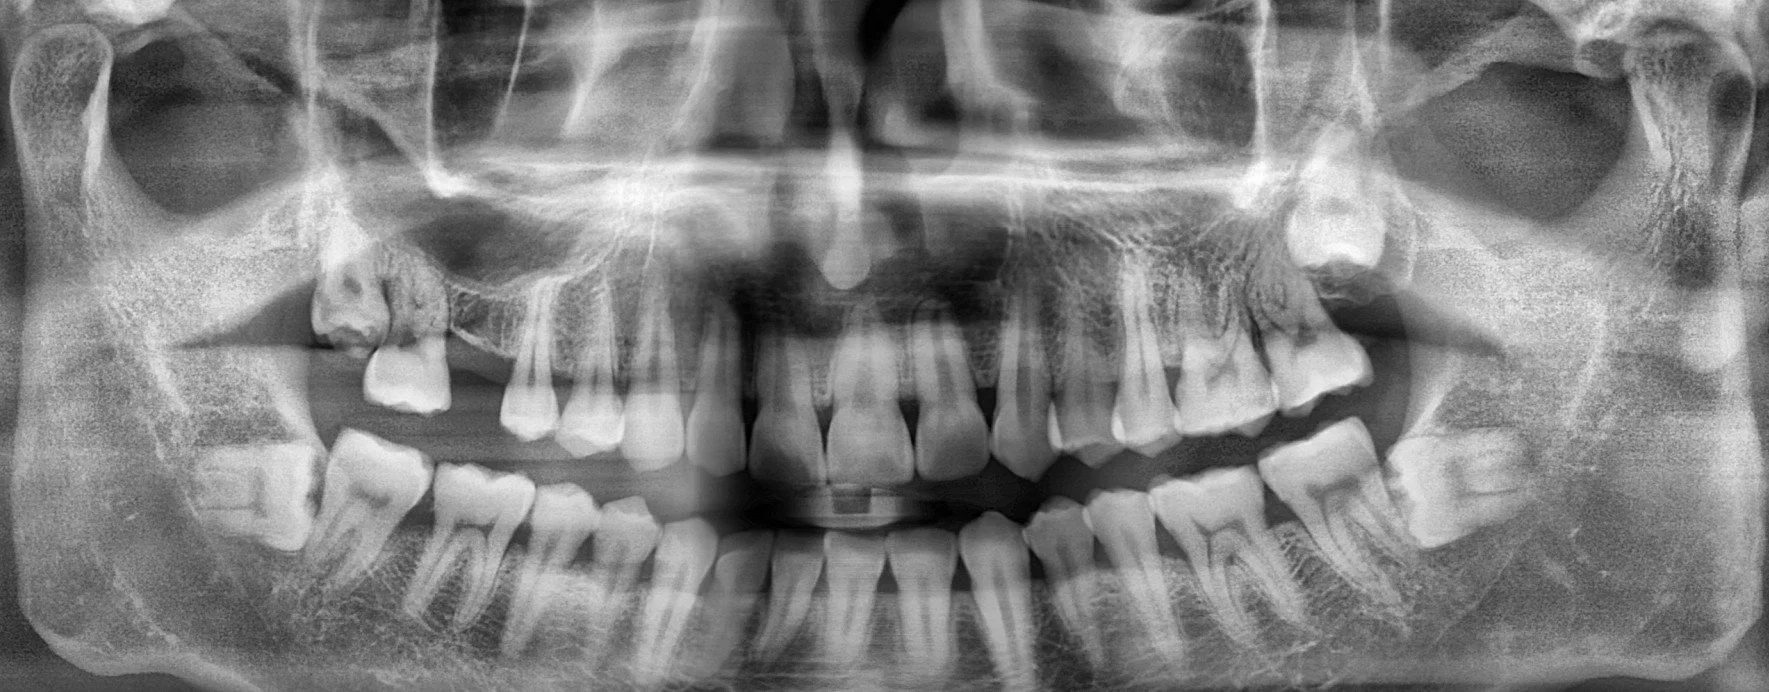

풍부한 임상경험과 노하우를 통해 3D CT를 이용한 모의수술을 통해 임플란트를 식립할 위치, 방향, 깊이 등

환자 개인의 수술 조건을 파악하여 맞춤형으로 오차를 줄인 정확하고 빠른 수술 시스템을 제공합니다.

CT촬영 및 구강 스캔

환자마다 구강구조, 신경의 위치 등이 달라

3D 디지털 장비를 이용하여 환자의

구강상태를 고려한 맞춤형 치료 계획 수립

디지털 시뮬레이션

치료 계획을 프로그램에 입력해

가상으로 시뮬레이션을 진행하여

모의수술을 통해 임플란트 식립 위치 설정

CT와 구강 스캔 데이터를 바탕으로 모의수술을 통해 임플란트 식립 위치를 결정하는 가이드 장치를 만듭니다. 가이드 장치를 사용하여 잇몸을 절개하거나 봉합하지 않고 간단한 수술이 가능합니다.